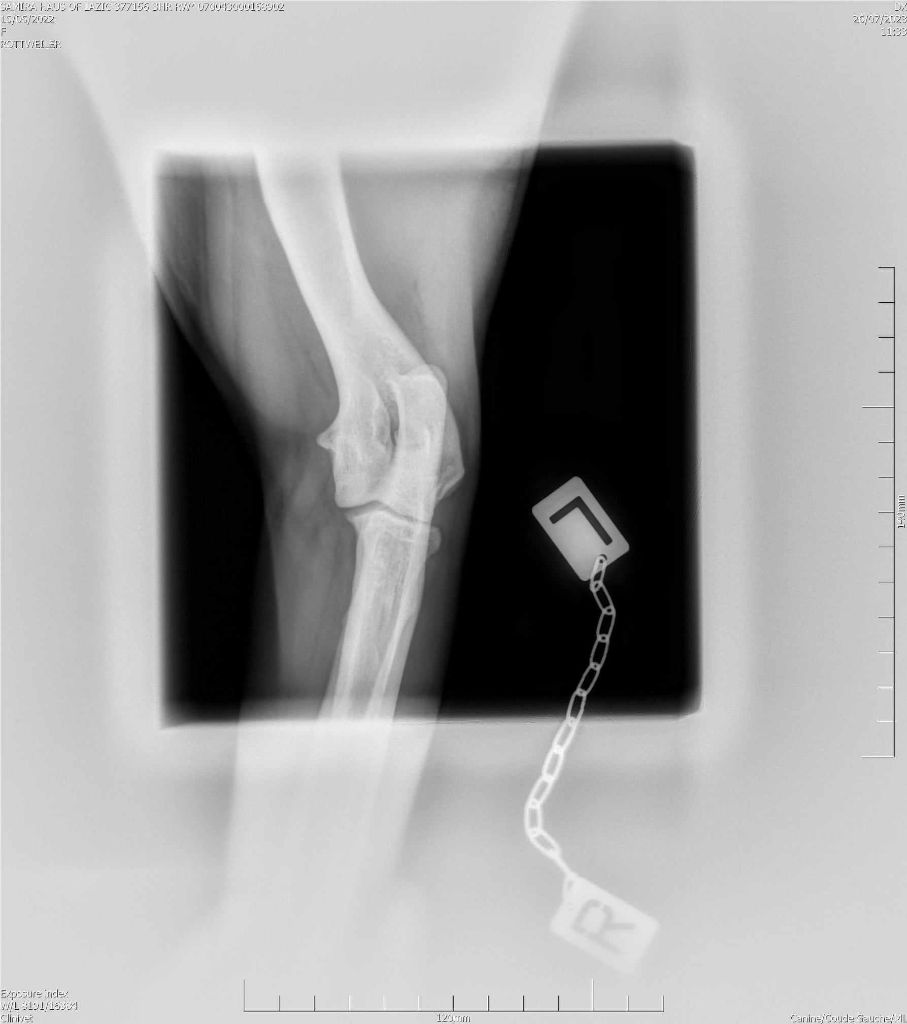

RADIO COUDE OFFICIELLE

COUDE SUITE

ADN : FAIT DYSPLASIE COUDES : ED0 DYSPLASIE HANCHES : HDA JLPP : CLEAR |